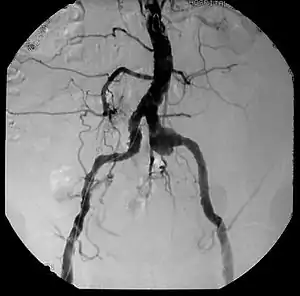

| Aneurysm, a commonly lethal complication of SA | |

| Complications | Aneurysm |

The infection often has no symptoms until the patient develops an aneurysm because of the aortic dilatation. The disease is often discovered after a routine checkup of the heart and aorta. Although is easy to be overlooked, other symptoms of tertiary syphilis might appear such as gummas and symptoms of neurosyphilis (headache, stiff neck, gait abnormality, dementia etc). Additionally, in rare cases, chest pain and shortness of breath might appear as a result of the damage of the aorta and heart valve.

Inflammatory involvement of tertiary syphilis begins at the adventitia of the aortic arch which progressively causes obliterative endarteritis of the vasa vasorum.[3] This leads to narrowing of the lumen of the vasa vasorum, causing ischemic injury of the medial aortic arch and then finally loss of elastic support and dilation of the vessel.[3] Dissection of the aortic arch is rare due to medial scarring. As a result of this advanced disease process, normal methods of angiography/angioplasty may be impossible for those with suspected coronary artery disease.